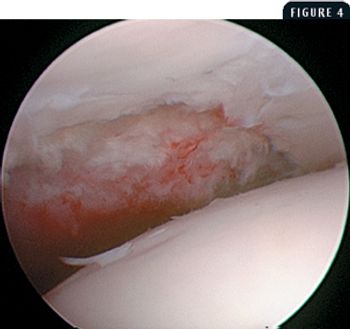

A 7-month-old intact male Labrador retriever was presented for evaluation of a two-week history of left hindlimb lameness.